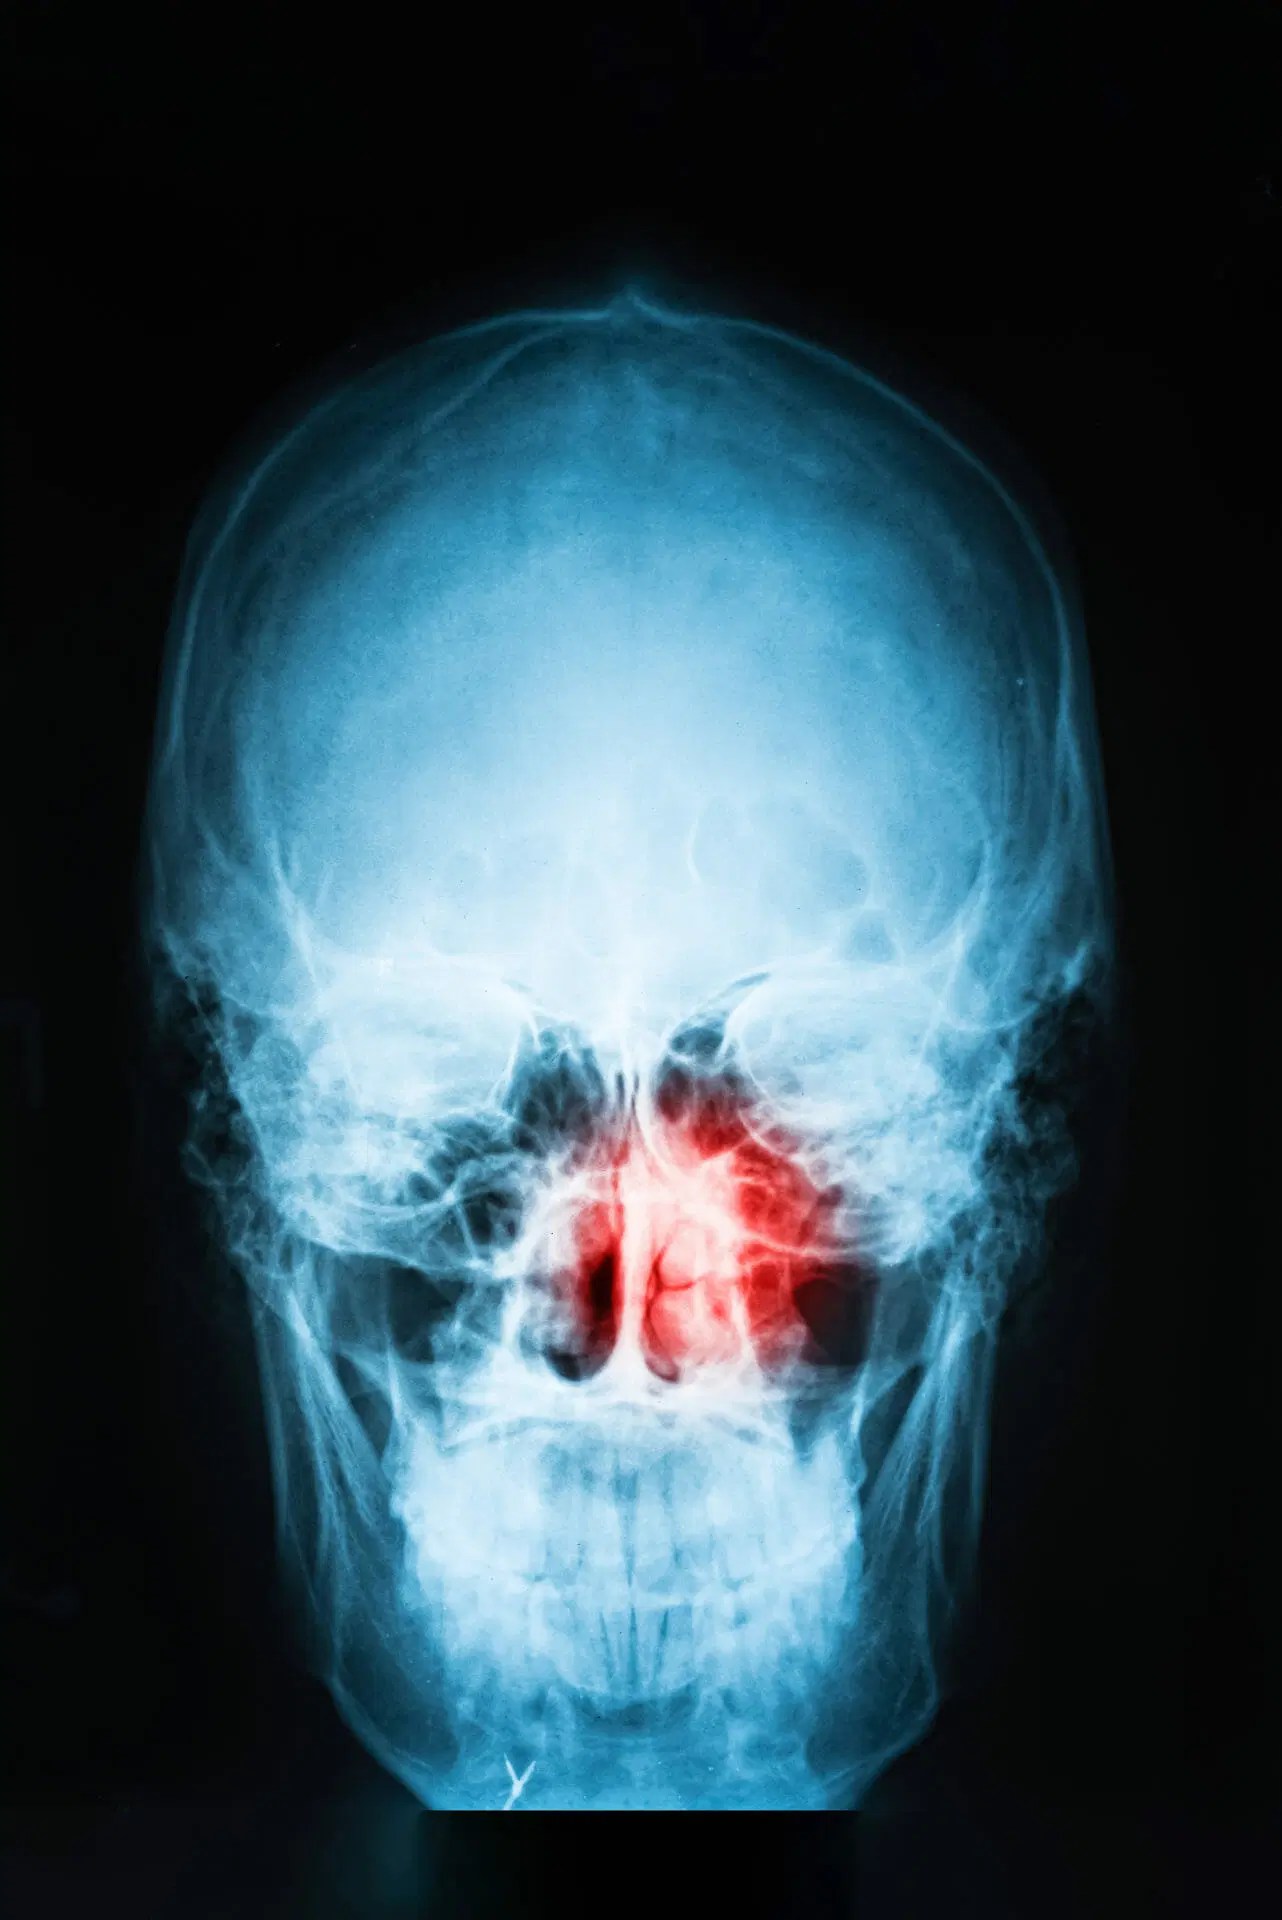

Nasal Cavity, Paranasal Sinus Cancer and Nasopharyngeal Cancer Woodworking Nasal Cancer Iarc states that wood dust causes cancer of the nasal cavity (nose area) and paranasal sinuses (spaces in and around the. Nasopharynx cancer (npc) and sinonasal cancer (snc) are two important cancers caused by exposure to wood dust. The current study aims to provide stronger evidence to aid in our understanding of the role of cumulative occupational exposure to. Woodworking Nasal Cancer.

Sinonasal undifferentiated carcinoma of the right nasal cavity Woodworking Nasal Cancer Nasopharynx cancer (npc) and sinonasal cancer (snc) are two important cancers caused by exposure to wood dust. Iarc states that wood dust causes cancer of the nasal cavity (nose area) and paranasal sinuses (spaces in and around the. The current study aims to provide stronger evidence to aid in our understanding of the role of cumulative occupational exposure to. Woodworking Nasal Cancer.

Sphenoid Sinus CT Scan Woodworking Nasal Cancer Nasopharynx cancer (npc) and sinonasal cancer (snc) are two important cancers caused by exposure to wood dust. The current study aims to provide stronger evidence to aid in our understanding of the role of cumulative occupational exposure to. Iarc states that wood dust causes cancer of the nasal cavity (nose area) and paranasal sinuses (spaces in and around the. Woodworking Nasal Cancer.

Sinus Cancer Signs, Symptoms, and Complications Woodworking Nasal Cancer The current study aims to provide stronger evidence to aid in our understanding of the role of cumulative occupational exposure to. Nasopharynx cancer (npc) and sinonasal cancer (snc) are two important cancers caused by exposure to wood dust. Iarc states that wood dust causes cancer of the nasal cavity (nose area) and paranasal sinuses (spaces in and around the. Woodworking Nasal Cancer.